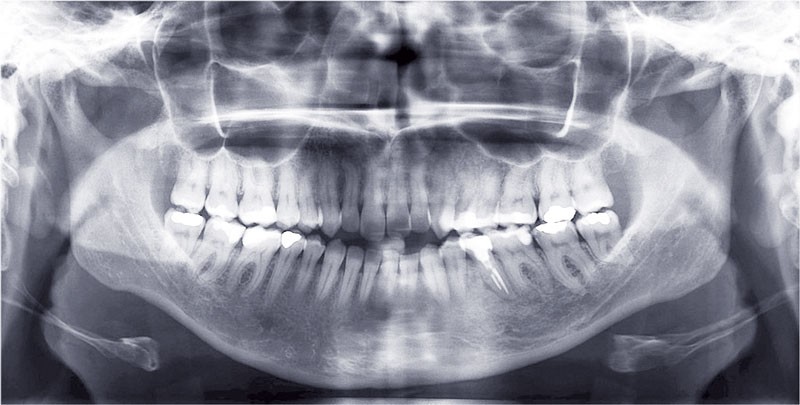

Le set up Insignia

Les empreintes ont été réalisées en sillcone wash technique et adressées au laboratoire Insignia. Actuellement, nous réalisons ces empreintes à l’aide de la caméra intra-orale Lythos et la fiche patient est initialement créée sur la caméra. Le transfert des empreintes au laboratoire est immédiat et le risque d’erreurs considérablement réduit (fig. 4 à 6).